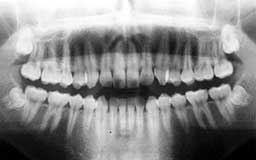

★ Pさん 52歳

年齢層をもう少し下げてみましょう。Pさんは来院時が52歳で、親知らずを除く喪失歯が

1本もなく健全そうにみえました。Oさん同様治療終了後の数年間にブランクがありました。

今から14年前の来院時にはメインテナンスを行うことの大切さがかなりはっきりわかってい

ましたので、それまでの経過を踏まえて少し強引にメインテナンスを勧めました。それ以降

はほとんど途切れることなくメインテナンスを継続されています。右の上顎第一大臼歯の1/3

だけ抜歯(ヘミセクション)していますので正確には現在残存歯数は27本と2/3ということ

になりますが、補綴(ほてつ)物も少なく10年後が楽しみな患者さんです。

| Pさん 初診時 52歳 男性 歯周疾患の進行傾向が随所に認められるが、年齢の割には比較的良好 |

Pさん 20年後 71歳 清掃状態は決して良好とはいえないが、20年間毎月メインテナンスを継続し良好な状態を保っている |